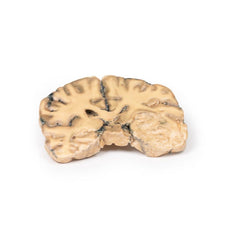

3D Printed Glioma Grade 3-4, Causing Papilloedema

The specimen shows a large intracerebral lesion, which has obliterated the lateral ventricles and

the inner 2/3 of the internal capsule and basal ganglia on the right side. It is infiltrating across the corpus

callosum and distorting the aqueduct. The tumour is fairly well demarcated and vascular with numerous areas of

haemorrhage and necrosis, causing its mottled variegated appearance.